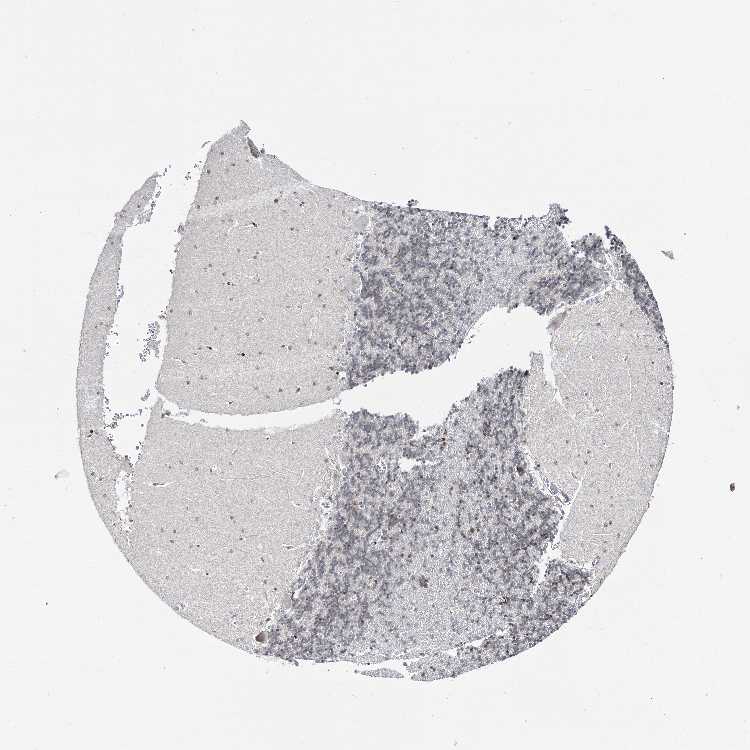

CEREBELLUM - Expression summary

CEREBELLUM - Antibody stainingi

Antibody staining in the annotated cell types in the current human tissue is reported as not detected, low, medium, or high, based on conventional immunohistochemistry profiling in selected tissues. This score is based on the combination of the staining intensity and fraction of stained cells.

Each image is clickable and will lead to virtual microscopy that enables deeper exploration of all samples and also displays staining intensity scores, fraction scores and subcellular localization as well as patient and tissue information for each sample.

Antibody HPA038664Antibody HPA038665

Purkinje cells LowMedium

Cells in granular layer MediumLow

Cells in molecular layer LowMedium